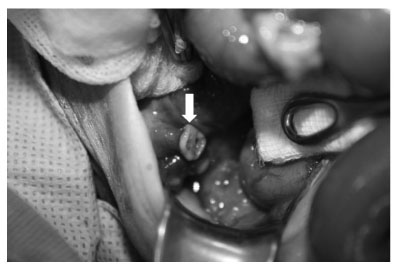

Preoperative supine(a) and cross-table lateral(b) abdominal X-ray show distension of bowel loops and free air in the peritoneum.

Fig. 1 Preoperative supine(a) and cross-table lateral(b) abdominal X-ray show distension of bowel loops and free air in the peritoneum.